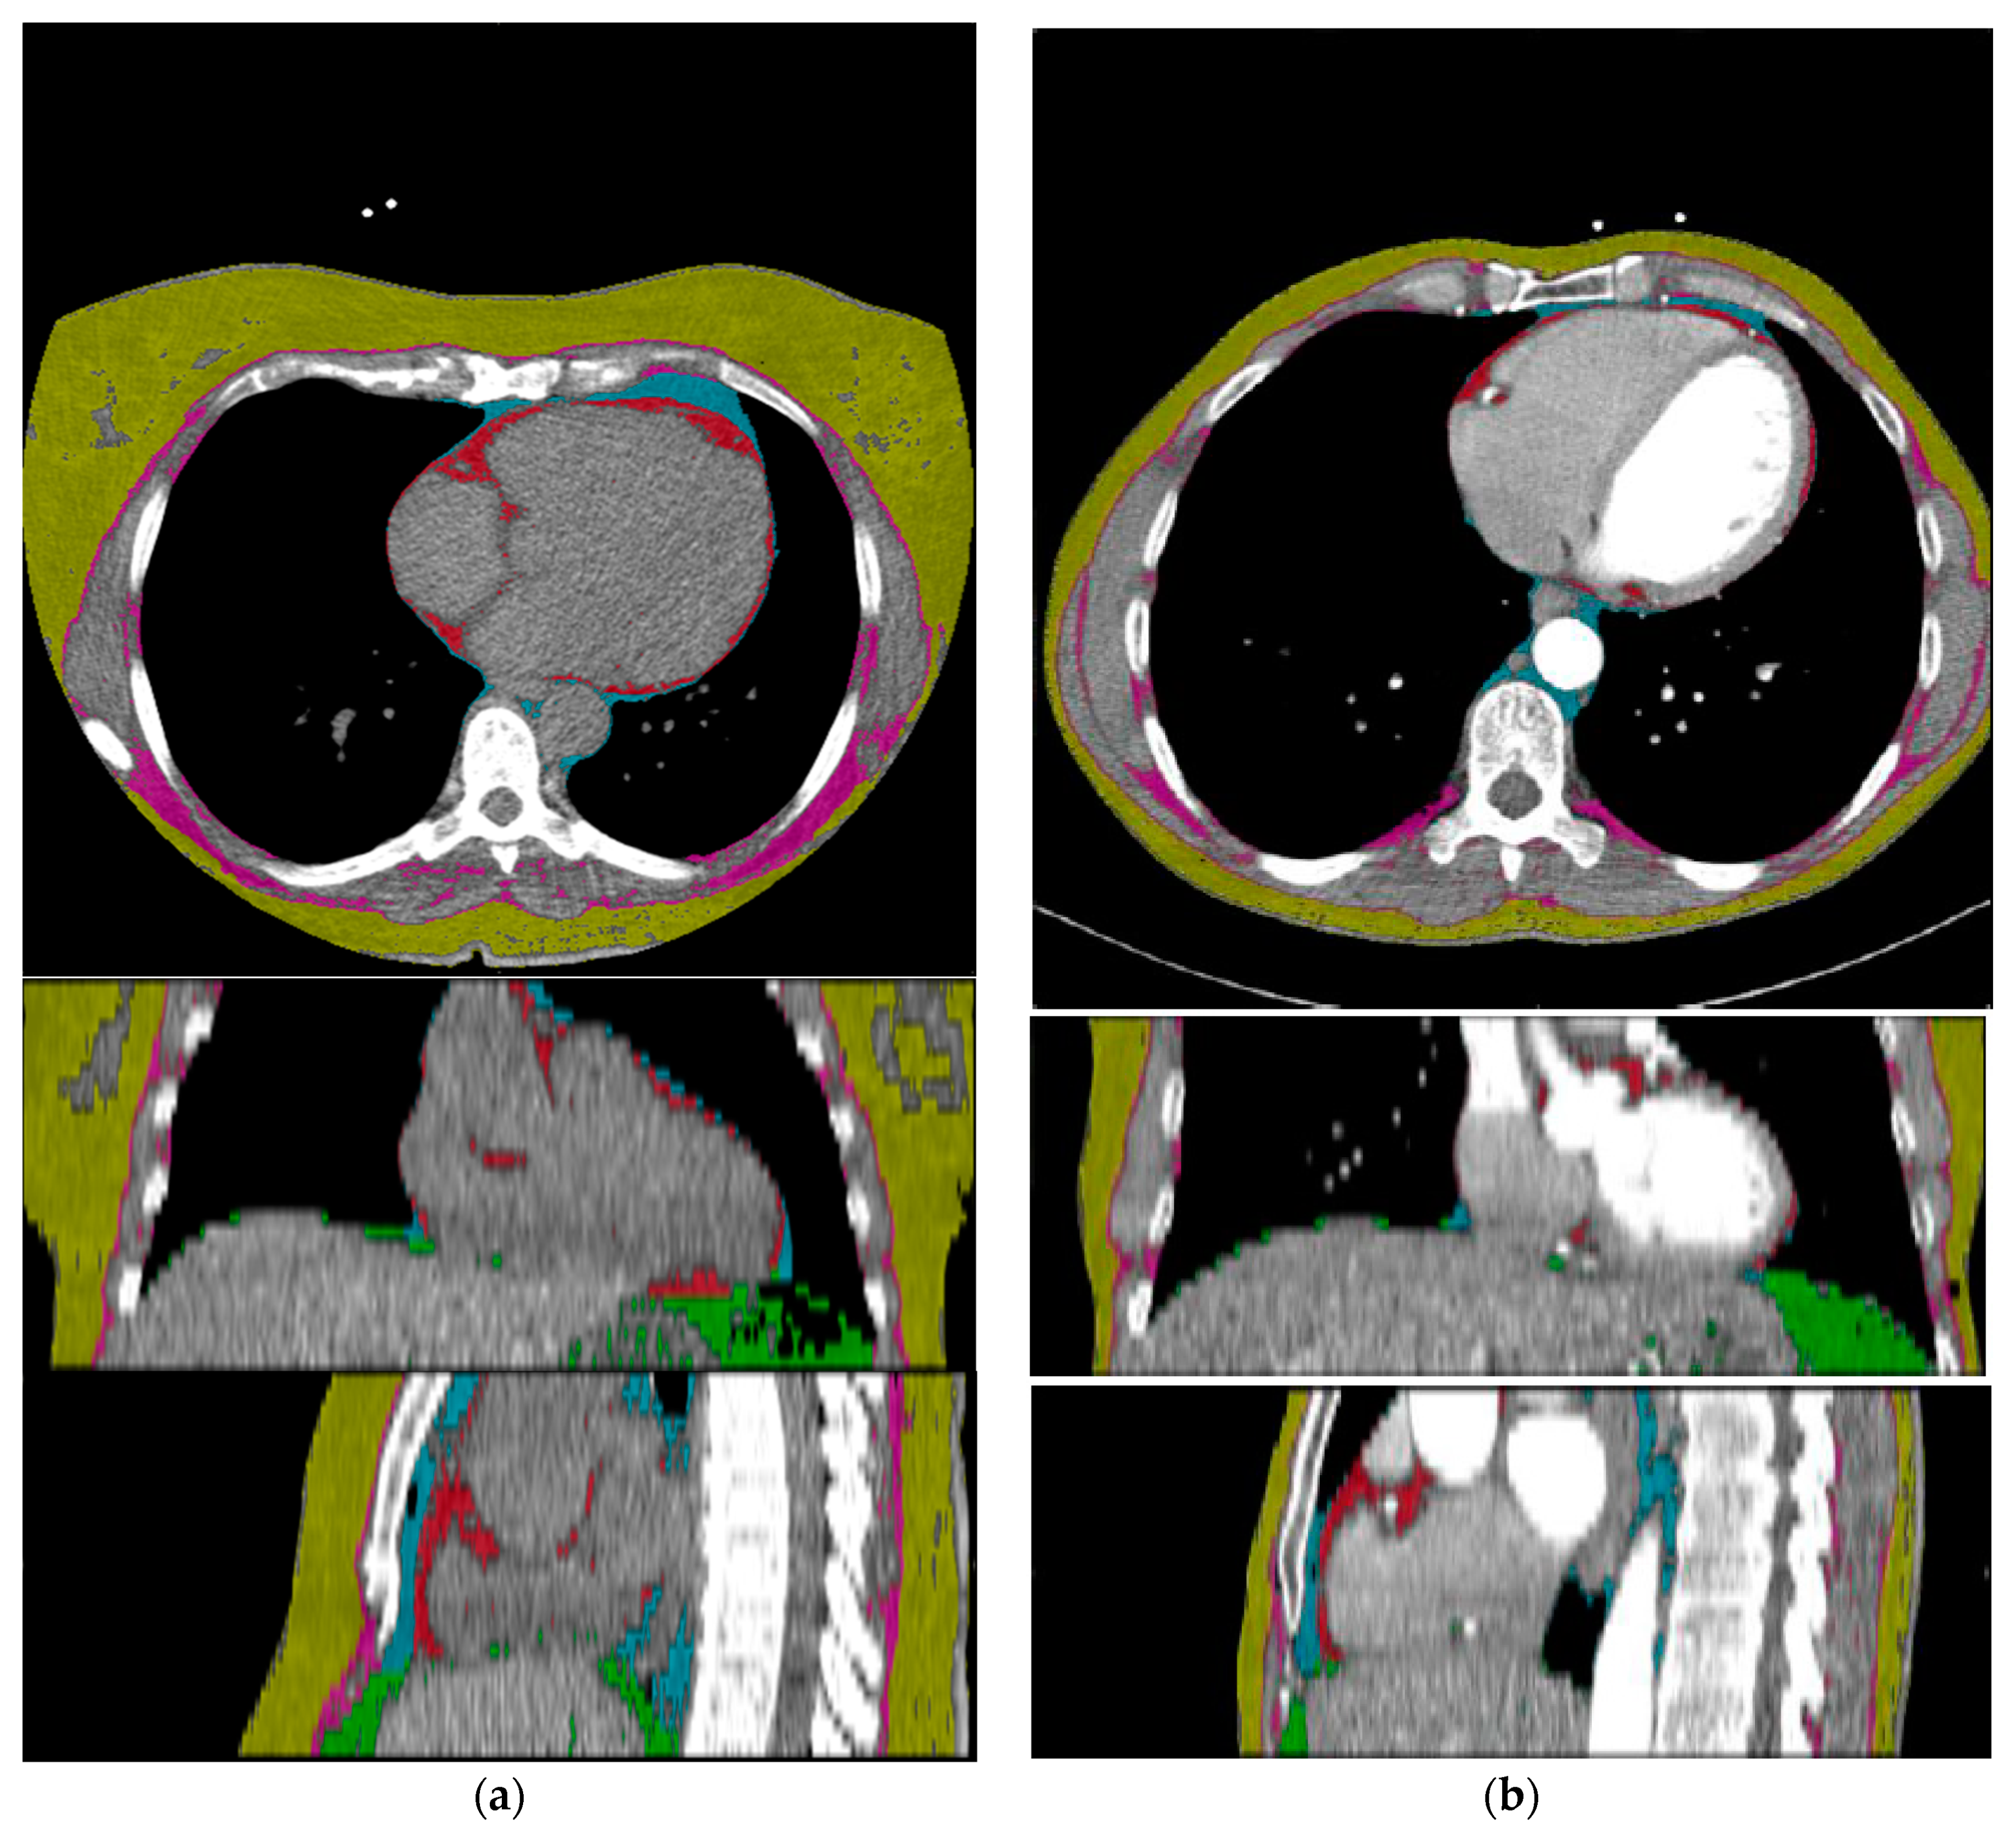

2.3. Deep Learning Architecture

2.4. Quantification of Epicardial Adipose Tissue